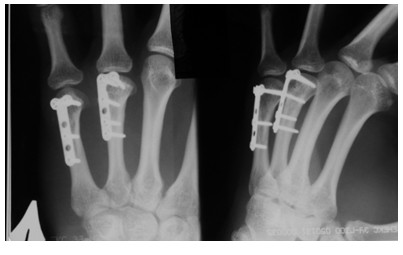

Рентгенограммы пациента со сросшимися переломами пястных костей, большеберцовой и бедренной костей после остеосинтеза

Функциональный результат у пациента со сросшимися переломами пястных костей, большеберцовой и бедренной костей после остеосинтеза